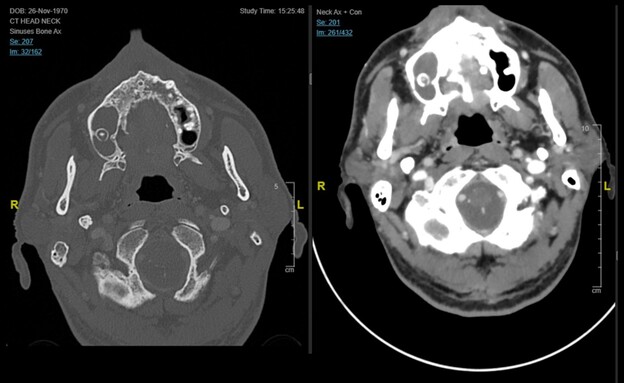

במהלך הבדיקה הבחין ד"ר מעלוף נסים, תורן מחלקת כירורגיה פה, פנים ולסתות, בממצא שנראה לכאורה זניח: כתם לבן-חיוור באזור החך. ד"ר מעלוף זיהה כי מדובר ברקמה נמקית והעלה חשד לזיהום פטרייתי פולשני, מצב חירום רפואי שבו הפטרייה חודרת לכלי הדם ומתפשטת במהירות למוח ולאיברים חיוניים. בתיאום עם הרופא הכונן, נלקחו דגימות דחופות והועברו למעבדה המיקרוביולוגית.

מיד עם קבלת הממצאים הוחל באופן מיידי במתן טיפול אנטי-פטרייתי ייעודי ואגרסיבי כדי לבלום את התפשטות הזיהום והמערכת נכנסה לכוננות שיא. בהמשך, בוצע ניתוח חירום מורכב על ידי ד”ר עבוד מבדא, רופא בכיר במחלקה לכירורגיית פה, פנים ולסתות, שכלל כריתה נרחבת של מחצית מהלסת העליונה והסינוסים, במטרה לעצור את התפשטות הנמק ולהגיע לשוליים בריאים.

"המקרה הזה הוא דוגמה מובהקת לכך שערנות קלינית של רופא במיון יכולה לשנות גורל של אדם", אומר פרופ' עימאד אבו אל נעאג', מנהל המחלקה לכירורגיית פה, פנים ולסתות, "עמדנו בפני דילמה רפואית קשה בגלל הרקע הרפואי המורכב של המטופל, אך היה ברור שהניתוח הוא הסיכוי היחיד שלו. נאלצנו לבצע כריתה נרחבת של מחצית מהלסת העליונה והסינוסים כדי לעצור את התפשטות הנמק ולהגיע לשוליים בריאים. עבודת הצוות בין הכירורגים, המעבדה והמרדימים הייתה הלב הפועם של הצלחת הטיפול הזה".